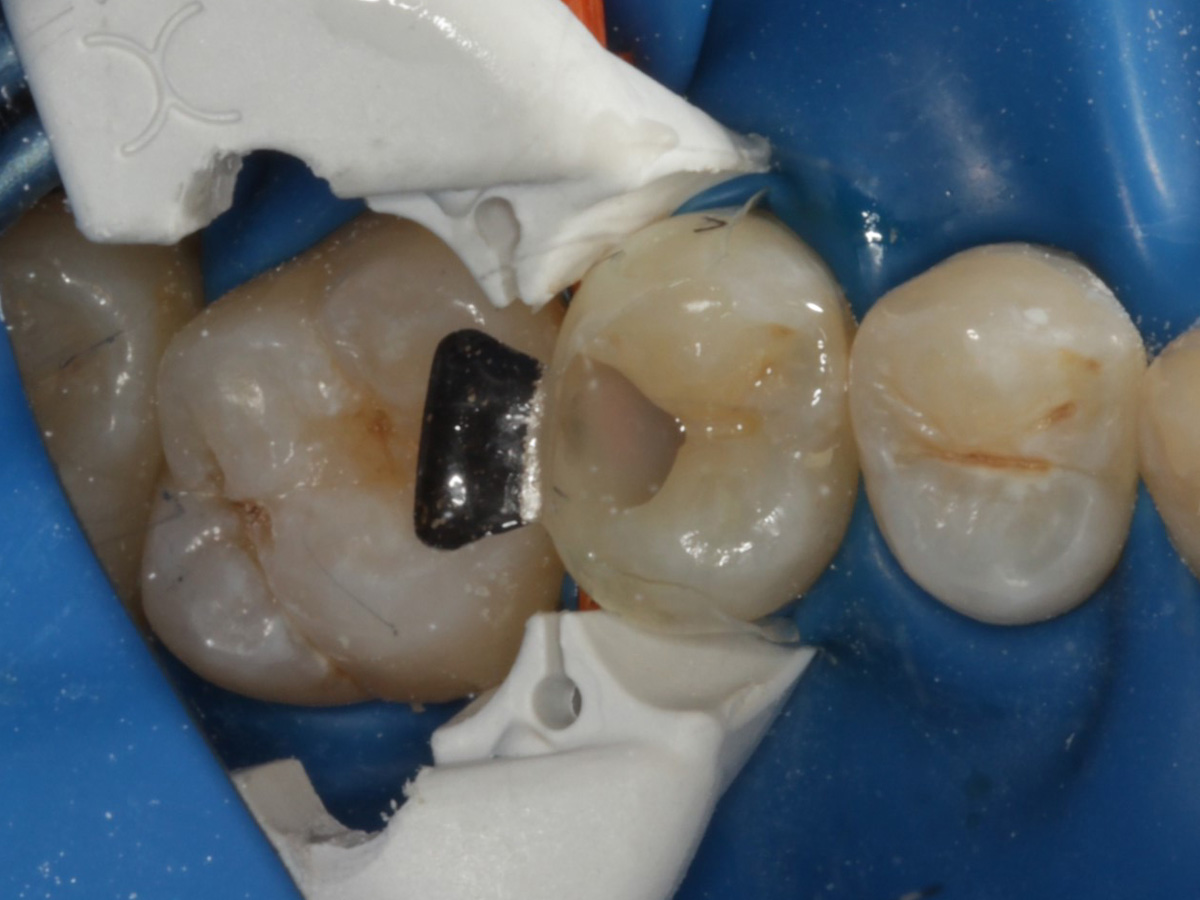

Abbildung 5

Defektdarstellung

Abbildung 6

Kariesexcavation pulpennah mit Kunststoffrosenbohrer